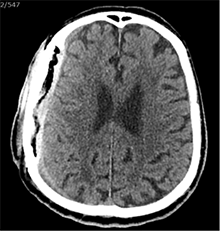

Praėjus dar 2 sav., pacientas iš slaugos ligoninės atvežtas dėl vangumo, dezorientacijos, nerišlios ir sulėtėjusios kalbos. Atlikus GKT, dešinėje pusėje po kraniotomijos lopu įtarta poūmė (ūmi) epidurinė hematoma, nesant VSD. Per parą pacientas operuotas. Operacijos metu po minkštaisiais audiniais rasta kraujo sankaupa su seroziniu komponentu, paimtas bakteriologinis pasėlis. Po KPL rasta krešulių su skystu krauju ir seroziniu komponentu. Paimtas antras bakteriologinis pasėlis, įtariant infekciją. Hematoma (seroma) pašalinta. Žaizda plauta mažos koncentracijos betadinu ir fiziologiniu tirpalu. Kraujavimo iš KSD nepastebėta. Nuspręsta KPL grąžinti – labiau tikėtina epidurinės seromos (EDS) diagnozė. Siekta uždaryti „negyvąjį“ epidurinį tarpą, pakabinant KSD centre prie KPL siūlais, tačiau KSD buvo nepaslankus, tampriai priaugęs prie smegenų. Atlikus kontrolinę GKT (9 pav.), nustatyta teigiamų pooperacinių pakitimų, smarkiai sustorėjęs KSD, tarpas tarp KPL ir KSD. VSD nenustatyta. Po operacijos paciento bendroji būklė buvo stabili. Reakcija buvo kiek sulėtėjusi, tačiau vyras gebėjo atsakyti į elementarius klausimus. Teigiama klinikinė dinamika. Po savaitės pacientas tapo labai vangus, sulėtėjo, skundėsi silpnumu, kalbėjo nesklandžiai. Pakartojus GKT (10 pav.), nustatyta padidėjusi epidurinė skysčio sankaupa, panaši į mišraus tankio hematomą (apie 64 ml tūrio) dešinėje pusėje frontotemporoparietaliai, padidėjusi VSD į kairę – iki 4 mm. Kadangi pacientas per tą patį randą jau operuotas 6 kartus, o po operacijų pastebimos vis atsinaujinančios pakartotinės EDS, priimtas sprendimas neskirti operacinio gydymo. KPL turėjo daugybinių perforacijų, todėl nuspręsta atlikti subgalinio tarpo punkciją, tikintis, kad per perforacijas išbėgs EDS. Atlikus punkciją, gauta 20 ml serohemoraginio skysčio. Po procedūros paciento būklė pagerėjo, jis tapo kiek aktyvesnis, tačiau efektas nebuvo patenkinamas. Kitą dieną nuspręsta punktuoti pakartotinai, gauta 4 ml serohemoraginio skysčio. Tūris buvo nepakankamas teigiamam efektui gauti. Priimtas sprendimas skirti lašinių infuzijų ir švelnią osmoterapiją neurologinei simptomatikai sumažinti. Punkcijos nedavė norimo efekto, todėl nuspręsta suformuoti poodinę neigiamo slėgio drenažinę sistemą po minkštųjų audinių lopu. Į subgalinį tarpą įvestas 20G periferinės venos kateteris, fiksuotas prie odos ir sujungtas su uždara vakuumine sistema, tikintis nuolatinio drenavimosi smegenų kompresijai sumažinti. Per 5 lovadienius išsiskyrė apie 50 ml serohemoraginio skysčio. Atlikus kontrolinę GKT, buvo matyti teigiama dinamika (11 pav.). Dėl infekcijos profilaktikos vakuuminė sistema pakeista 2 kartus. Įvedus vakuuminę sistemą, po 12 lovadienių paciento būklė pagerėjo, jis tapo aktyvesnis, į klausimus atsakydavo prasmingai, paliepimus vykdydavo visomis galūnėmis. Vakuuminė sistema pašalinta. Po 2 dienų atlikta GKT (12 pav.). EDS dešinėje pusėje regresavo, smegenų kompresijos nenustatyta. Esant stabiliai būklei ir teigiamai dinamikai, pacientas grąžintas į slaugos ligoninę.

10 pav. Bėgant laikui, padidėjusi EDS (dešinėje F-T-P, padidėjusi VSD į kairę iki 4 mm)